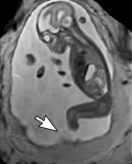

During image acquisition the fetus is not sedated and moves freely as well as the mother breathes normally. As a result, movements are likely to corrupt the scans, hiding pathology and causing overlap between different anatomical regions. In order to limit these artifacts, fast scanning sequences such as ssFSE [10] allow for the rapid acquisition of single slices at high in-plane resolution in a large field of view and good tissue contrast of the uterus. However, when acquiring a 3D volume through a stack of slices, inter-slice artifacts in the out-of-plane views are highly likely. Consequently, this restricts reliable diagnostics to individual slices in the current clinical practice. Fig. 1 depicts a typical example of motion related artifacts in a fetal single-shot fast spin echo (ssFSE) scan. The observed motion (c.f. Fig. 1 b & c) is of unpredictable nature and consists of a combination of maternal respiration movements, fetal movements and bowel movements.

Reconstruction of Fetal Organs: Exemplary PVR and SVR reconstructions under motion introduced by kicking of the fetus are shown in Fig. 11. PVR reconstruction results show an improved visual appearance and less blurring in the region with severe motion artifacts (arrow). An example of a challenging clinical case with a kidney malformation in one of twin fetuses, is shown in Fig. 8. Our clinical partners confirmed that such complications are easier to examine and to quantify after PVR-based reconstruction.